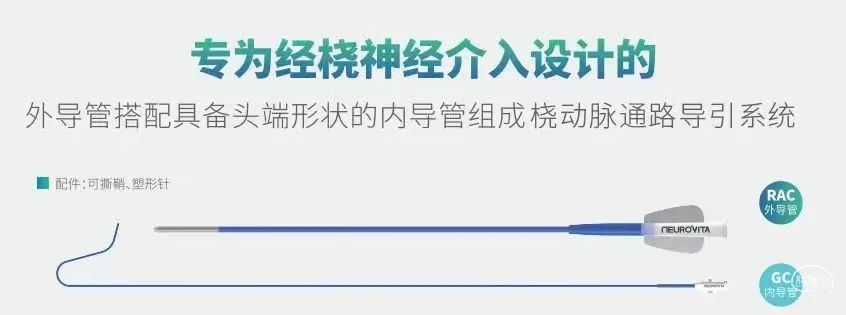

赛诺经桡通路系列产品

桡动脉通路导引系统产品介绍

针对不同规格,更合理的分段设计: